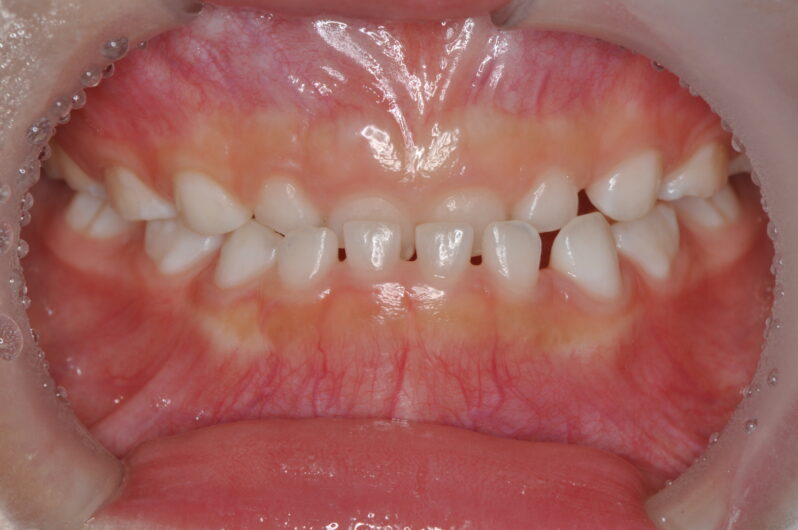

今回の女の子も初診時にははっきりと反対咬合の状態でした。このまま成長すると、治療が難しくなることが予測されました。

術前写真